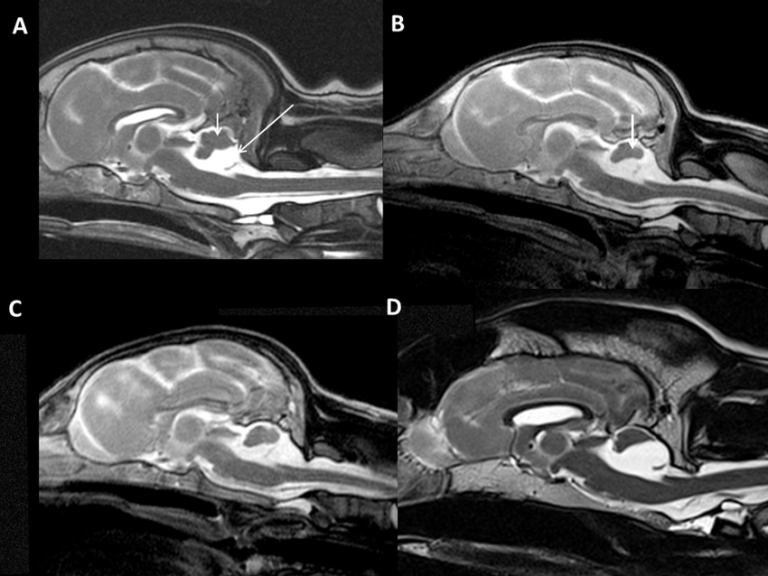

Een CT-scan is een geavanceerde beeldvormingstechniek waarbij met behulp van röntgenstralen gedetailleerde dwarsdoorsnedebeelden van het lichaam worden gemaakt. De scanner maakt honderden opnames vanuit verschillende hoeken, die door de computer worden samengevoegd tot driedimensionale beelden. Zo kunnen we de inwendige structuren van uw dier – zoals botten, organen en weefsels – uiterst precies in beeld brengen.

- Hoofd en hersenen: onderzoek naar tumoren, ontstekingen, tand- en kaakproblemen of neurologische afwijkingen.